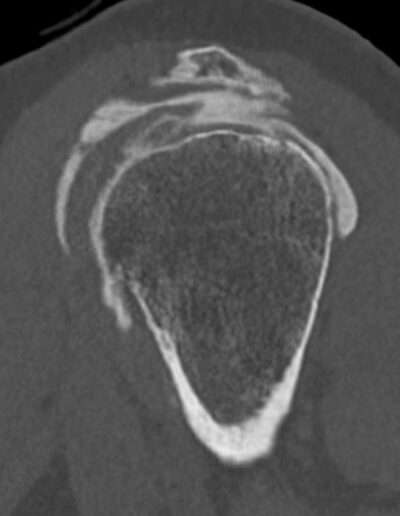

Shoulder Left

Patient 37 y/o, Male, right-handed

• 2005: Spontaneous episodes of subluxation – recurrence every year

• 01/2024: Posterior dislocation, reduced in ED